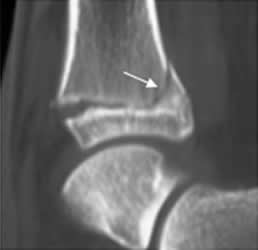

Fig 71. Salter tipo I.

Rx AP. Esclerosis e irregularidad en las placas de crecimiento del peroné, por cicatrización de lesión Salter tipo I.